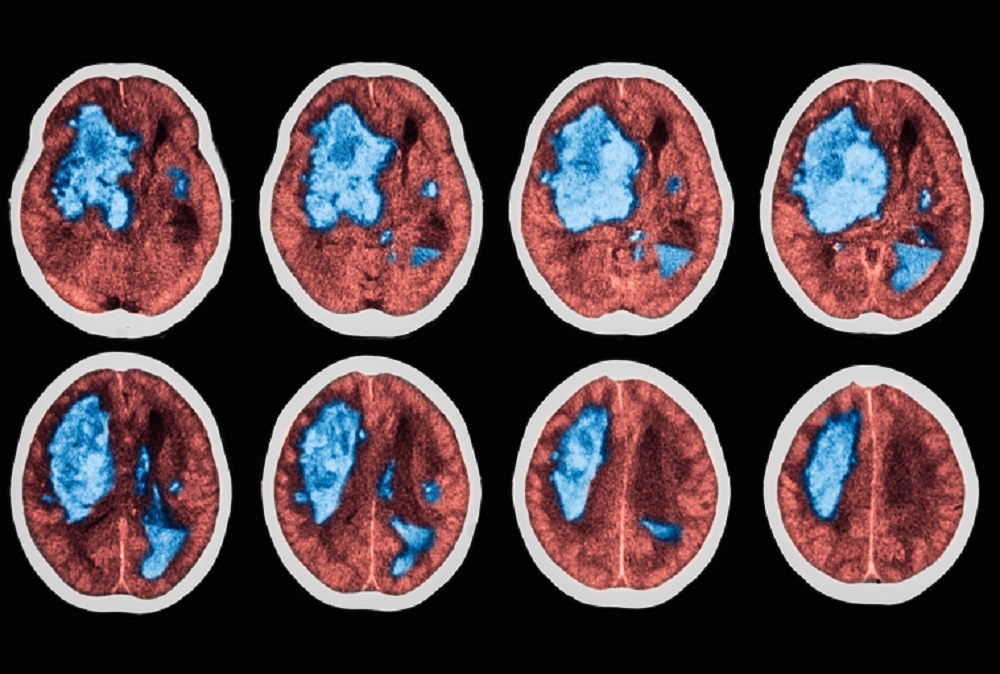

Subclinical AF and Increased Stroke Risk: Is There a Clear Connection?

A recent meta-analysis found there is insufficient evidence supporting the link between some forms of subclinical atrial fibrillation and an increased risk of thrombotic events.

The average lifespan is increasing in most parts of the globe, triggering a corresponding increase in the prevalence of atrial fibrillation (AF) across many demographics.1 Symptomatic AF is known to significantly increase lifetime risk of thrombotic events (TEs), and general wisdom supports the use of oral anticoagulants (OACs) in patients with symptomatic AF.

However, many clinicians struggle to determine whether OAC is an appropriate treatment for subclinical atrial fibrillation (SCAF). According to a meta-analysis published in Biomedical Papers, there is insufficient evidence supporting the link between some forms of SCAF and an increased risk of TE. The meta-analysis concludes that clinicians must judge each patient’s risk factors to determine if anticoagulant therapy is appropriate.1